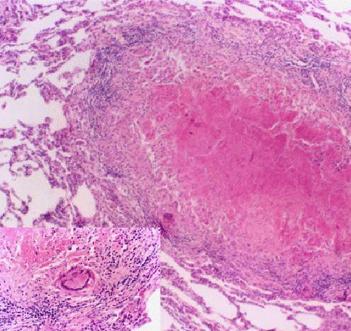

本病多见于童年期,它可以是原发的,也可能是继肠结核或肺结核而续发的。在原发病例,其细菌大都是直接透过健康的肠壁而进入淋巴结,或者是肠壁的原有病变已经完全愈合未留痕迹。在继发病例,则大多数在肺或肠有明显的病灶。淋巴结受累最多的是在回盲部,在盲肠及升结肠内侧的腹膜后间隙中,以及在小肠系膜下端部分。偶尔,上腹部的淋巴结也可以有结核性病变。随着病期的不同,受累的淋巴结可以有急性肿大,呈干酪变,化脓,或者硬结钙化等不同的变化。有些钙化的淋巴结可以坚硬如结石,在X线检查时与肾脏结石或胆囊结石甚为相似,常需通过肾盂造影或胆道造影才能鉴别。有些淋巴结的干酪变或冷脓肿可相互融合成团,其大如拳,须开腹探查方能鉴别。